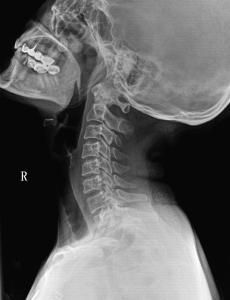

頸椎失穩症又稱頸椎不穩症。頸椎失穩是指頸椎在生理載荷下,解剖上超出其生理限度的位移範圍,且出現相應的臨床症狀引起的一種綜合徵。隨著現代生活的日益緊張,其發病率呈上升趨勢,並成為頸肩痛、頭暈痛、胸悶,甚至雙上肢麻脹痛更為常見的原因。

頸椎失穩人體頸椎的穩定性系由兩大部分來維持:一是內原性穩定,包括椎體、椎弓及其突起、椎間盤和相連的韌帶結構,為靜力性平衡;二是外原性穩定,主要為頸部肌肉的調節與控制,它是脊柱運動的原始動力,為動力性平衡。上述任何一個環節遭受破壞,均可能引起或誘發頸椎正常結構及平衡功能的喪失,從而導致頸椎不穩。

頸椎的穩定性在力學範圍內用剛度來衡量;當頸椎因各種原因導致其結構功能減退時,活動節段的剛度就會降低,於是在生理載荷下便會出現過度活動和(或)異常活動,這就是頸椎失穩;若由此引起一系列相應的臨床表現,並且存在潛在的進行性畸形和神經損害的危害,就稱為頸椎失穩症。在諸多病因中,退行性變最為常見。椎間盤是人體組織中發生退行性變最早的部位。主要表現為蛋白多糖和水分含量的減少以及非膠原蛋白成分的增加。